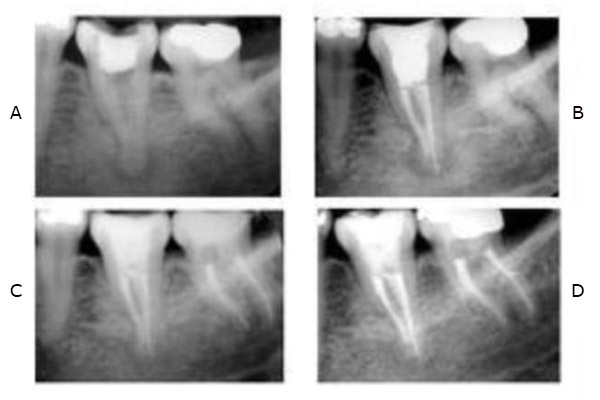

3. ENDODONCIA

La Endodoncia o tratamiento de conductos se encarga del tratamiento de las enfermedades que afectan al tejido pulpar del diente (también conocido como “ nervio” ).Gracias a éste tratamiento se puede preservar dientes que antiguamente había que extraer . La endodoncia se indica en casos de caries muy profundas ( lo más común ),dientes fracturadoso por indicación protésica.

Endodoncia o tratamiento de conductos